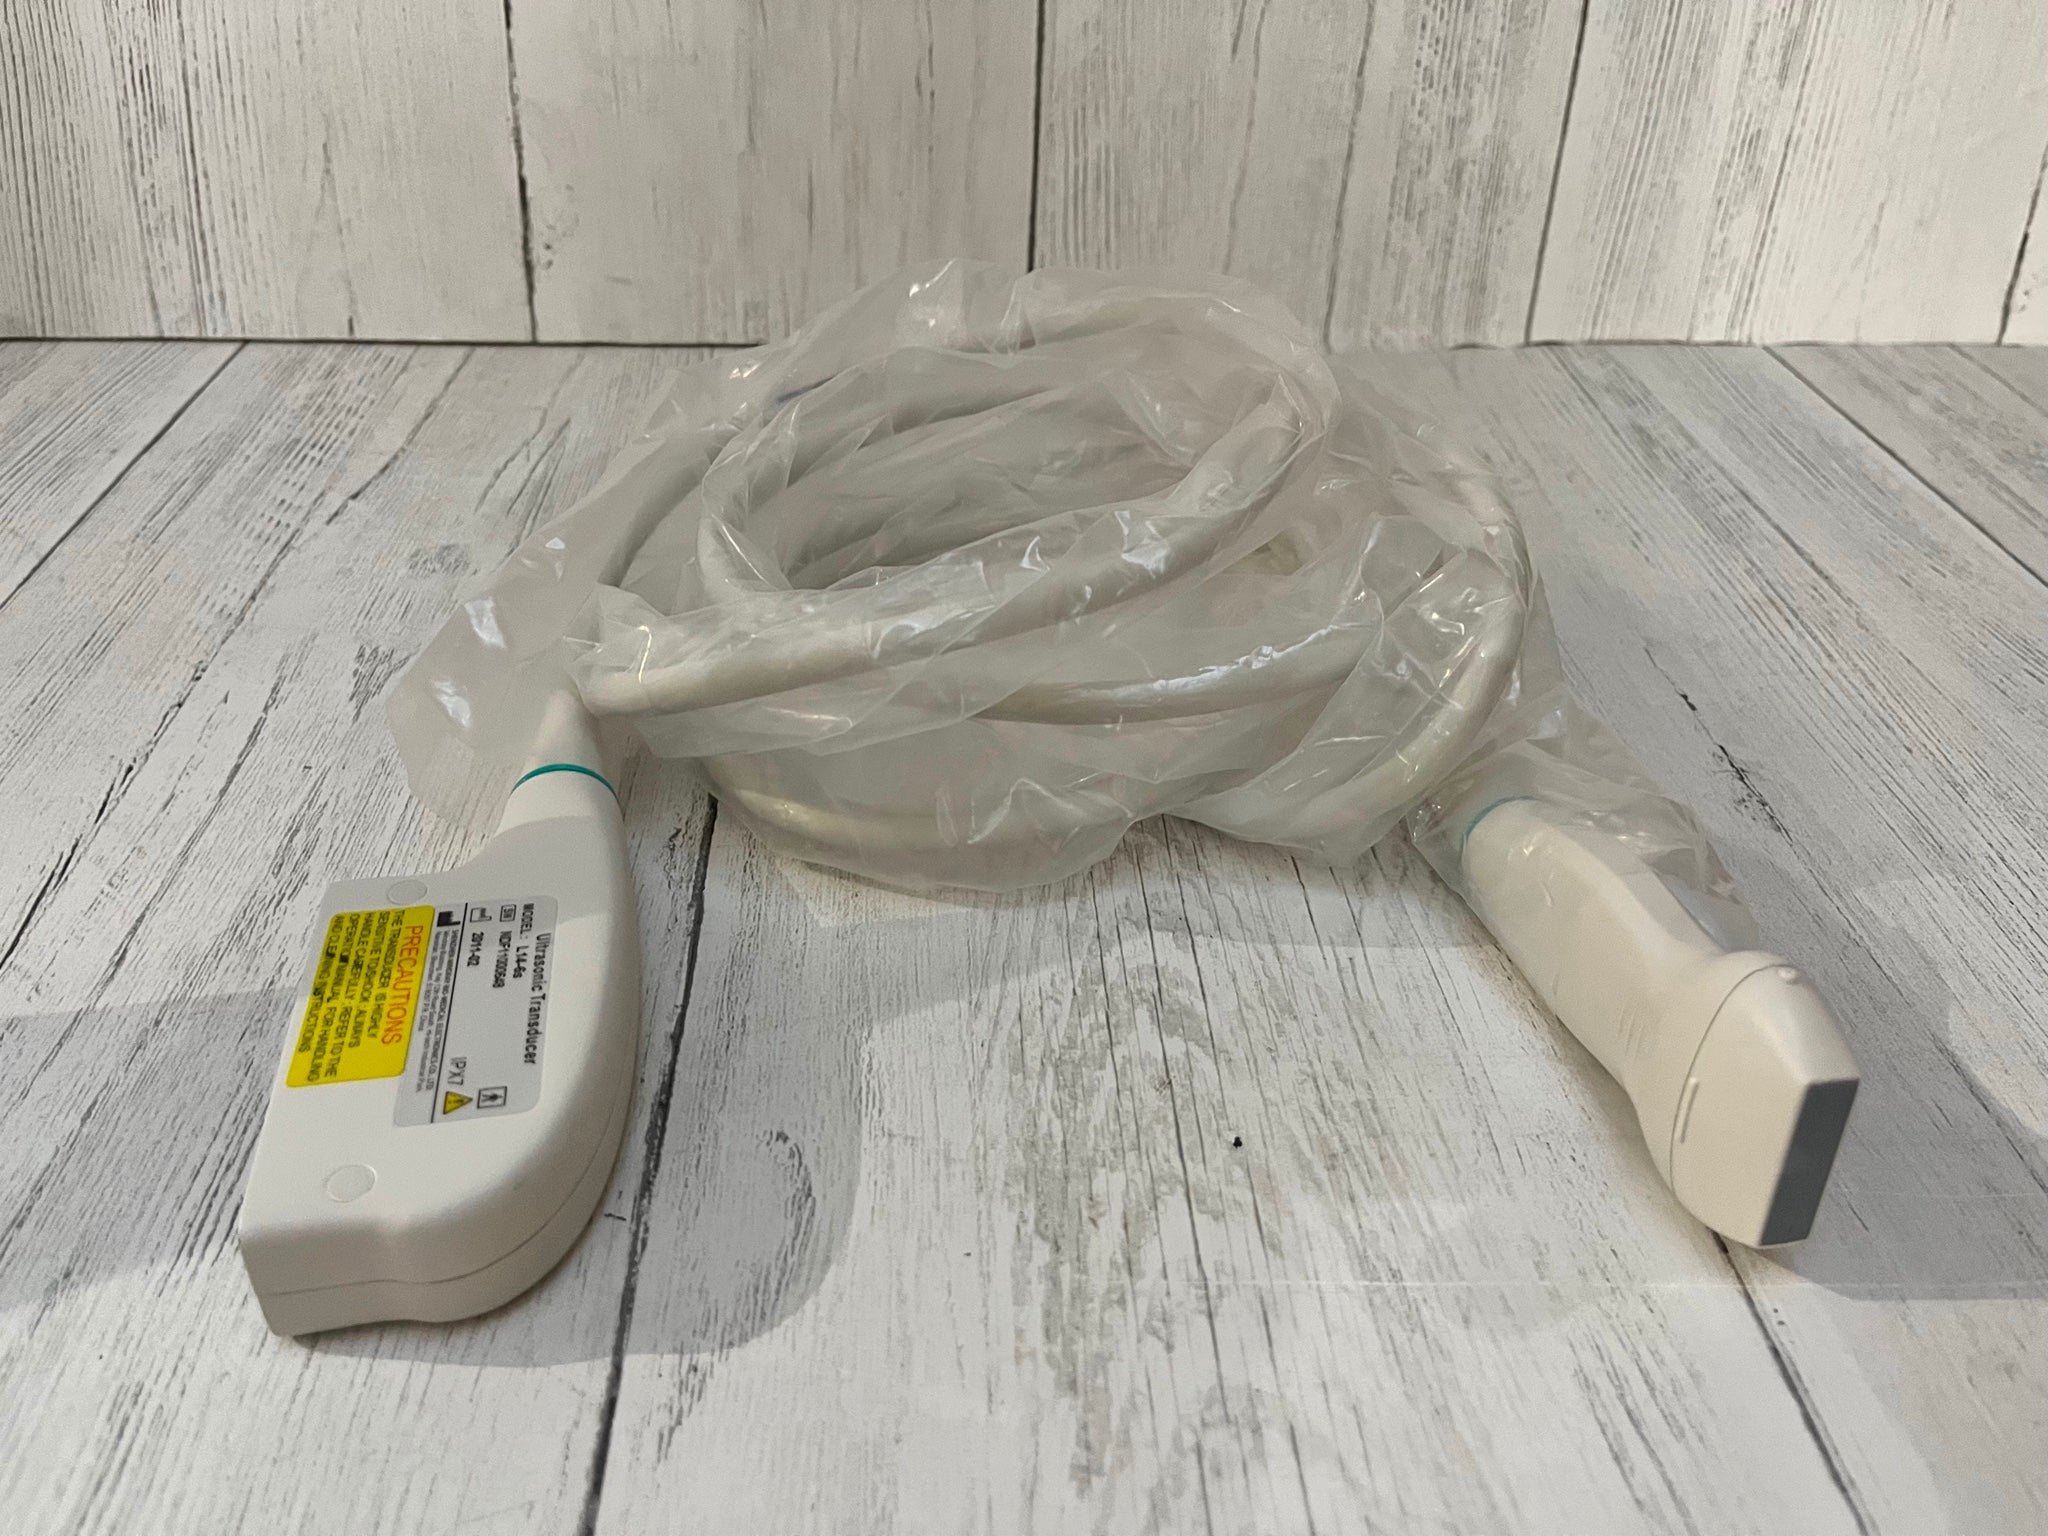

Seller Notes:âFully functional. Tested using a GE Logiq 9 with a breast phantom. Shows signs of use. Includes everything shown.â

Model: GE 4D8C 3D/4D Curved Array 3.5-9MHz Ultrasound Tra

The GE 4D8C ultrasound transducer probe operates within a frequency range of 3.5-9MHz, making it ideal for high-resolution imaging. This device harnesses advanced 4D capabilities, allowing healthcare professionals to visualize complex anatomical structures in real-time. Consequently, it enhances diagnostic accuracy and aids in better patient care. Users can expect clear and detailed images, which significantly improve evaluation and treatment processes.

This ultrasound transducer is versatile and adapts to various clinical applications, including obstetrics, cardiology, and vascular imaging. Medical practitioners can utilize the instrument for routine examinations and specialized diagnostics. Another advantage is its curved array design, which provides an extended field of view, allowing for easier and quicker assessment of the patient's condition. Hence, it streamlines workflows in busy clinical environments.

The GE 4D8C ultrasound probe integrates user-friendly features that make it easy to operate, even for novice users. The ergonomic design ensures comfort during long procedures, while the intuitive controls provide a seamless experience for the operator. Additionally, the device is lightweight, promoting ease of handling. Therefore, healthcare providers can maintain focus on patient outcomes, knowing that they have reliable equipment at their disposal.